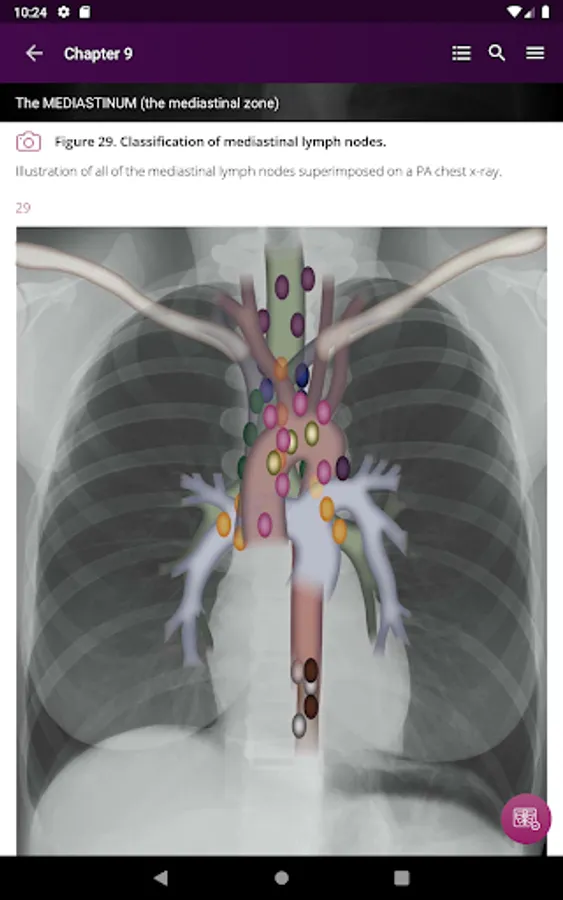

Section II* introduces the concept of radiological zones to give you a starting point in the understanding of the radiological anatomy of the chest. The next chapters review in detail the radiological anatomy of specific anatomical structures, also provide examples of how the x-ray image can change due to pathology. The final chapter explains how the individual structures come together to form the radiological image.